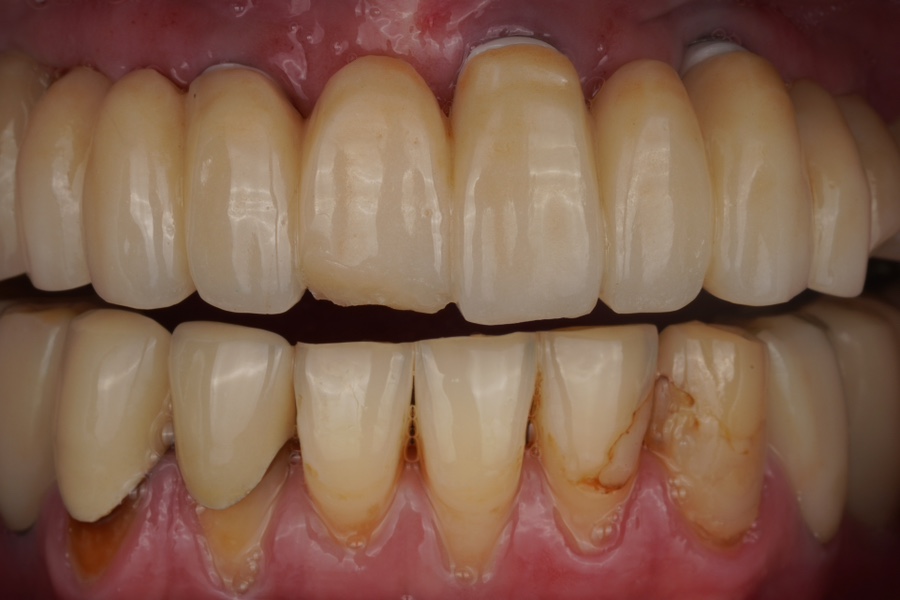

보철물 앞니가 깨지셨는데 저희치과에서 그거 수리해준다 들으셨다며 전화로 예약하고 찾아와주신 분입니다. 처음 오셨을때 상태 지르코니아 보철 수리는 대부분 지르코니아 파우더를 adding하여 치과용 가마(퍼니스)에서 구워내야하는데 지르코니아 코어 위에 도자기(포세린)를 올려 만들어낸 PFZ보철물같은 경우 레진으로도 수...

출처 아카이브 열기보철물 앞니가 깨지셨는데

저희치과에서 그거 수리해준다 들으셨다며

전화로 예약하고 찾아와주신 분입니다.

처음 오셨을때 상태

지르코니아 보철 수리는 대부분

지르코니아 파우더를 adding하여

치과용 가마(퍼니스)에서 구워내야하는데

지르코니아 코어 위에

도자기(포세린)를 올려 만들어낸

PFZ보철물같은 경우 레진으로도 수리가 가능해요.